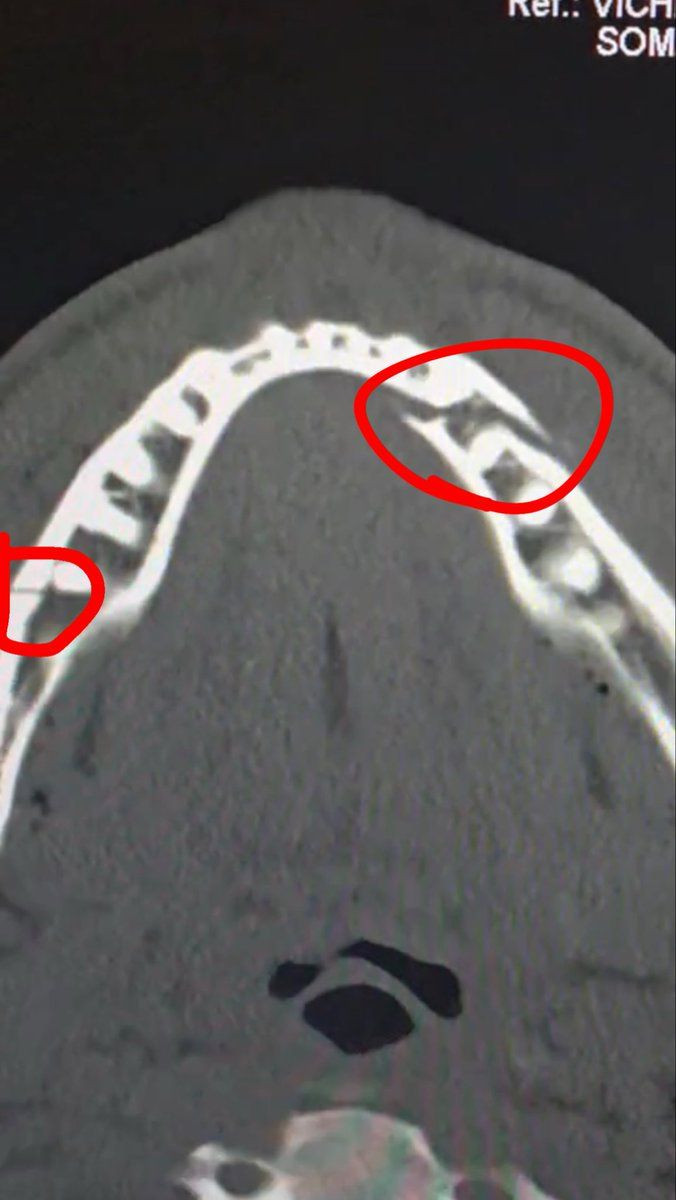

Несмотря на травму, Пол заявил, что по-прежнему горит желанием драться: "Двойной перелом челюсти. Дайте мне Канело через 10 дней".

Он также добавил, что перенес операцию: "Только что вышел из операции. Все прошло хорошо. Мне поставили две титановые пластины с обеих сторон челюсти. Удалили несколько зубов. Спасибо за вашу поддержку. Чувствую сильную боль и скованность. Следующую неделю буду питаться жидкостями. Огромное спасибо замечательной команде Университета Майами. Все были очень добры и заботливы", - написал Пол в своей социальной сети.